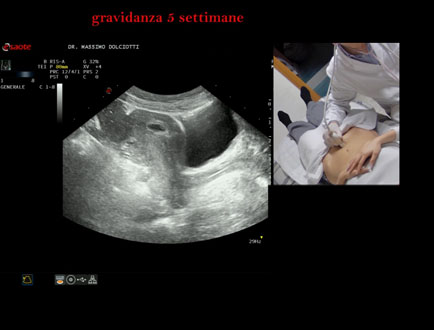

Data inserimento: 06/02/2026

Ecografia del: 28/01/2025

Strumento: Esaote MyLab Eight

Sonda: Convex Multifrequenza 1-8 MHz

Età Paziente: F 28 anni

Motivazione dell'esame: amenorrea.

Commento all'esame: le immagini ed il video documentano la camera gestazionale delle dimensioni di 11 mm e presenza di embrione delle dimensioni di 4,1 - 5,4 mm, con iniziale battito cardiaco.

Conclusioni: gravidanza alla quinta settimana di gestazione (pregnancy in the 5th week of gestation).

In collaborazione: Dr.ssa Marica Manfredi - Ancona, Dr. Ilir Qose - Ancona

Presentazione: Dr. Massimo Dolciotti - Ancona

Elaborazione digitale: Andrea Dini - Ancona